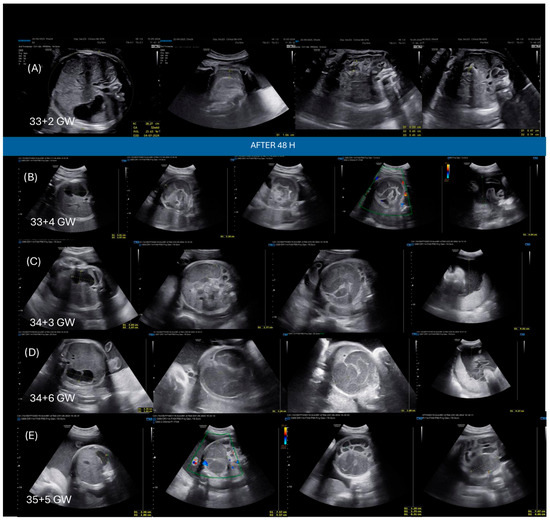

Introduction: Cystic fibrosis (CF) frequently presents prenatally with meconium ileus (MI), a condition associated with significant neonatal morbidity and long-term gastrointestinal complications. The advent of highly effective CFTR modulators, particularly elexacaftor/tezacaftor/ivacaftor (ETI), during pregnancy remains off-label, and their role as in utero therapy for affected fetuses of carrier mothers is still emerging. Methods: We conducted a narrative literature review using PubMed, Embase, and Scopus to identify published reports of in utero CFTR modulator therapy for MI between 2022 and 2026. Seven relevant studies were identified and qualitatively synthesized. Their findings were interpreted in comparison with the present case. Results: We describe the first Italian case of prenatal ETI therapy for fetal CF. At 32 weeks’ gestation, ultrasound (US) findings were suggestive of evolving MI. Both parents were carriers of F508del CFTR and subsequent testing confirmed fetal homozygosity. Following urgent multidisciplinary consultation and ethics committee approval, maternal ETI therapy was initiated at 33 weeks’ gestation. After 21 days of treatment, follow-up fetal US demonstrated improvement in bowel dilatation and hyperchogenity. The infant was delivered at 36 + 2, passed meconium spontaneously, and required no surgical intervention. Pharmacokinetic assessment showed substantial transplacental transfer of all three ETI components, with cord-to-maternal plasma ratios of 0.34 (elexacaftor), 2.48 (tezacaftor), and 0.58 (ivacaftor), and detectable concentrations in amniotic fluid. Postnatally, sweat chloride was elevated, and pancreatic function transitioned from initially preserved to pancreatic insufficiency within the first month of life. Conclusions: This case and literature review suggest that prenatal CFTR modulation may influence the early trajectory of CF, potentially by preventing MI and potentially delaying the progression to pancreatic insufficiency and potentially reducing later gastrointestinal complications. While evidence remains limited, these findings highlight a potential therapeutic window during fetal life and underscore the need for prospective data collection, structured registries, and harmonized clinical guidance in this evolving field. Full article